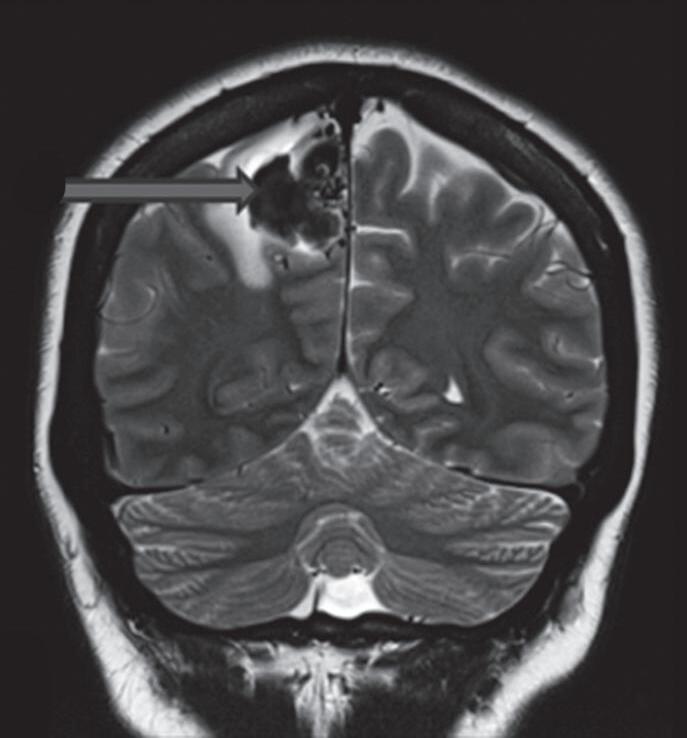

Fig. 1-15. RNM encéfalo T1 (a) sagital sem contraste e (b) axial com contraste demonstrando MAV grau 3, parcialmente embolizada, localizada no giro temporal superior e lobo parietal direito. (c) Arteriografia cerebral em perfil, demonstrando a irrigação pelos ramos da artéria cerebral média e posterior, com drenagem superficial nas veias de Labbé até o seio sigmoide, e o complexo de Trolard no seio sagital superior. O nidus da MAV está demonstrado pelas setas azuis grandes e a drenagem venosa pelas pontas de setas.